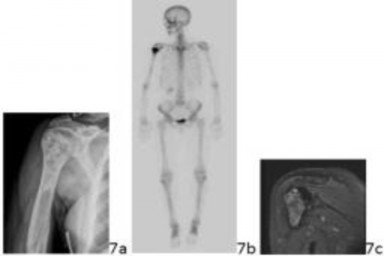

5. # .7a 7b 7c A 52-year-old woman has had progressive shoulder pain for the past 18 months. She has pain at night that awakens her from sleep, and a constant ache in her shoulder that has required narcotics for pain control. She has a history of fracture following an automobile accident 15 years prior that healed without incident. Figures 7a through 7c show the radiograph, bone scan, and T2-weighted coronal MRI scan of the proximal humerus. Based on this information, what is the most likely diagnosis?

DISCUSSION: The images reveal a mineralized lesion of the proximal humerus that has the classic appearance of a chondroid lesion with the "rings and arcs" densities typically seen on a radiograph. The bone scan

shows increased uptake in this area, consistent with an active lesion. The MRI scan confirms a lobular lesion that is bright on the T2-weighted scan and fills the bone. This, in combination with the history and age of the patient, is strongly suggestive of a malignant chondroid lesion, or chondrosarcoma. Whereas a bone infarct has mineral density on radiographs, it tends to be more "smoke up the chimney" or wispy in appearance, and is usually not hot on bone scan and not symptomatic. Ewing's lesions are destructive lytic lesions without the mineralization as seen here. Fibrous dysplasia similarly lacks this mineralization pattern, but has the "ground glass" or "hazy"

appearance and is rarely symptomatic. Osteosarcoma typically appears in younger patients and has a generally more

destructive appearance with "cloud-like" mineralization from bone formation, as compared with the "rings and arcs" mineralization seen in chondroid lesions.Prefer Response to Question # 7 is 4.